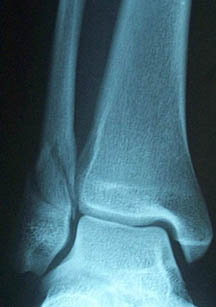

About half way around the loop came off the bike real bad, landing off a ski jump and catching my right foot under the bike as I landed. I managed to get a lapped rider to help me up and start my bike.

I tried to twist me foot in line again because I thought it was dislocated but it didn't straighten. It was a freak accident and it wasn't even sore and the bike was fine. I try rejoined the race but couldn't put any pressure on it. I just idle back to the pits and into the ambulance.

I got taken to a local hospital in Wairoa then discharged later that day. I wanted to be fixed up closer to home. I was in Waikato hospital for four nights and had surgery on my ankle. They also found that I had a broken tibia.